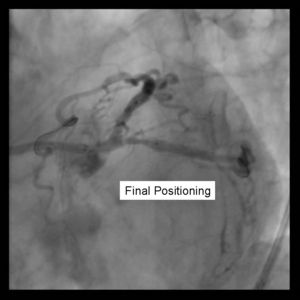

4) Using 2 Insufflators, both stents are inflated to low pressure. Then alternating with side branch and parent branch inflated to optimal deployment size. There is some risk of

over sizing the main branch with the overlapping stent segments. In the case where proximal disease may interfere with the 2 overlapping stents, a proximal stent may be

deployed prior to inflating the 2 distal stents. (Pants-and-trousers technique)